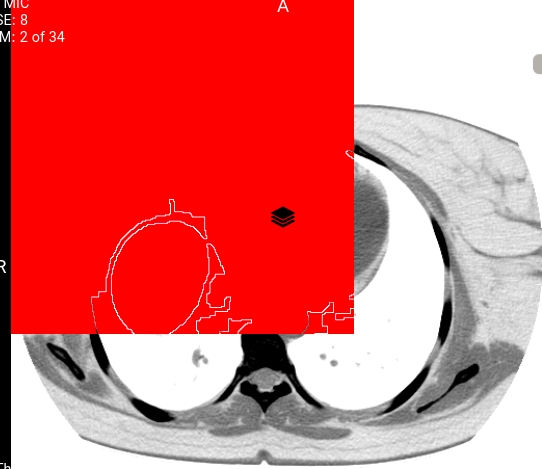

Hi thanks for the excellent work. I have a problem with the overlay show. 1 2 my overlay and my base image (512 x 512), But overlay is displayed up to 370 x 370. These are my objects Overlay: overlayData.overlays.push({ rows: 512, columns: 512, type: '', x: 0, y: 0, pixelData: pixedlData, description: undefined, label: undefined, roiArea: undefined, roiMean: undefined, roiStandardDeviation: undefined, fillStyle: 'red', visible: true }); Image : cachedLut: {lutArray: Uint8ClampedArray(4156), windowWidth: 400, windowCenter: 40, invert: false, voiLUT: undefined, …} color: false columnPixelSpacing: 0.646484 columns: 512 data: n {byteArrayParser: {…}, byteArray: Uint8Array(197792), elements: {…}, warnings: Array(0)} decodeTimeInMS: 78 floatPixelData: undefined getPixelData: ƒ () height: 512 imageId: "" intercept: -1024 invert: false loadTimeInMS: 1492 maxPixelValue: 2155 minPixelValue: -2000 rowPixelSpacing: 0.646484 rows: 512 sharedCacheKey: "" sizeInBytes: 524288 slope: 1 stats: {lastGetPixelDataTime: -1, lastStoredPixelDataToCanvasImageDataTime: -1, lastPutImageDataTime: -1, lastRenderTime: 0.09499999950639904, lastLutGenerateTime: -1} totalTimeInMS: 1573 width: 512 windowCenter: 40 windowWidth: 400

Screenshots

Before before After after